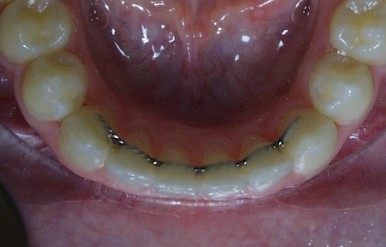

bonded.jpg (22395 bytes)A bonded retainer is normally placed on the tongue side of the lower teeth after the braces are removed. It is a wire bonded to the teeth with composite. It is important to floss under the wire daily with floss threaders. Sometimes this type of retainer will be used for the upper teeth, but normally this is not possible because it would interfere with your bite. A bonded retainer will remain in place for several years. Eventually Dr. Martin will remove this retainer and place a traditional wire retainer. Usually the bonded retainer is removed after the wisdom teeth have either erupted or been removed.